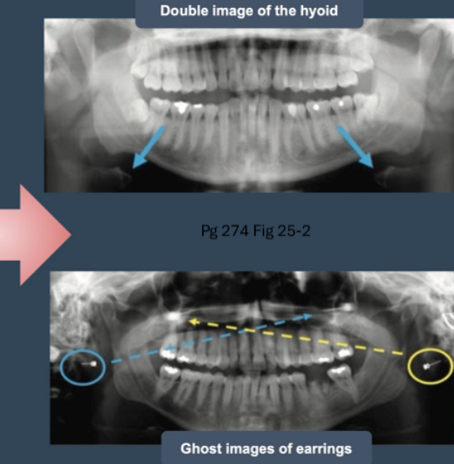

what is a double image

when structure is located behind the moving rotation center

what is the difference and similarity between a double and real image

double image is mirror but has the same proportions as a real image

what is a ghost image

structure located close to pt but outside the focal source ; appears blurred and magnified on opposite side of true angle

what are artifacts

motion

double images

ghost images

what causes ghost images

glasses, jewelry, retainers, etc